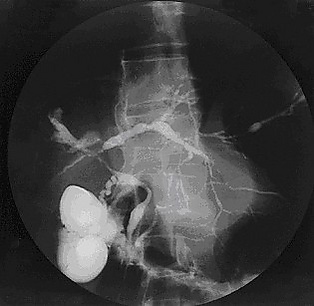

Даже при отсутствии симптомов со стороны кишечника необходимо исключать язвенный колит (и реже болезнь Крона) с помощью ректороманоскопии и биопсии слизистой оболочки прямой кишки. Колит, как правило, носит хронический, диффузный характер лёгкой или средней степени тяжести. Активность холангита обратно пропорциональна активности колита, а ремиссии обычно длительные. ПСХ может быть выявлен как раньше, так и позже, чем колит. Наличие язвенного колита не влияет на течение первичного склерозирующего холангита[9]. С целью определения тяжести и распространённости поражения проводится эндоскопическая ретроградная холангиопанкреатография — метод выбора, хотя с успехом может быть использована чреспечёночная холангиография. Диагностическим критерием считается выявление участков неравномерного сужения и расширения (чёткообразность) внутри- и внепечёночных жёлчных путей[9].